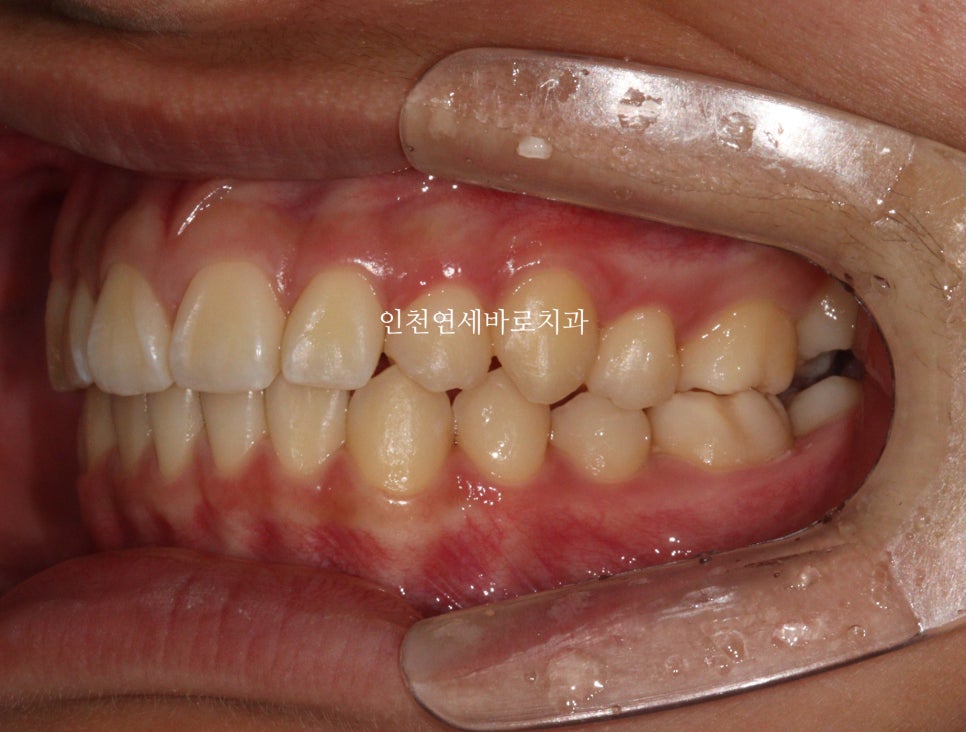

2024년 10월 – 치료 완료

중심선도 잘 맞고

교합도 양호합니다.

최후방 어금니는 맹출 중 입니다.

화살표 부분의 치아 순서가 일반적인 순서와는 조금 다르지만

기능적, 심미적으로 거의 문제없이 해결했습니다.